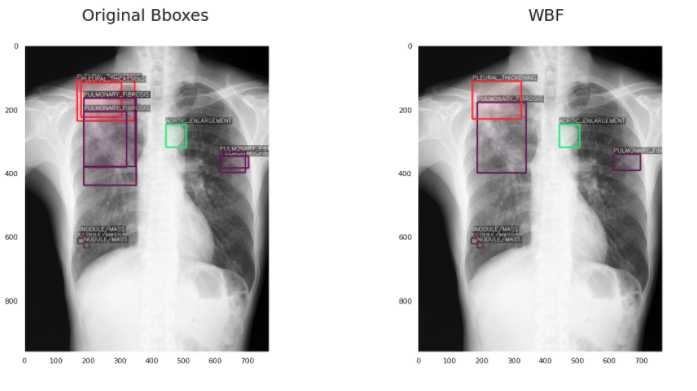

5、加权框融合(WBF)后处理,0.226 mAP (+15%)

这对我来说也是一个全新的想法,在网上很难找到。加权框融合是一种对目标检测模型产生的框进行过滤,从而使结果更加准确和正确的技术。它的性能超过了现有的类似方法,如NMS和soft-NMS。具体内容我会在另一篇文章介绍。

应用WBF的结果是这样的: